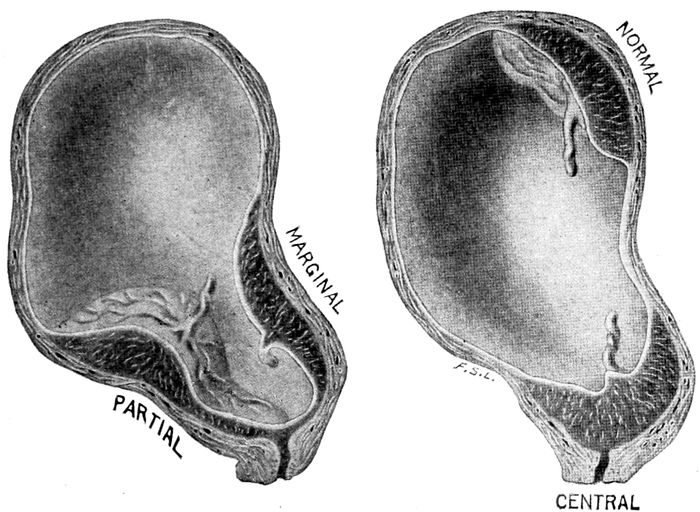

| 99. |

Various forms of placenta prævia |

229 |

| |